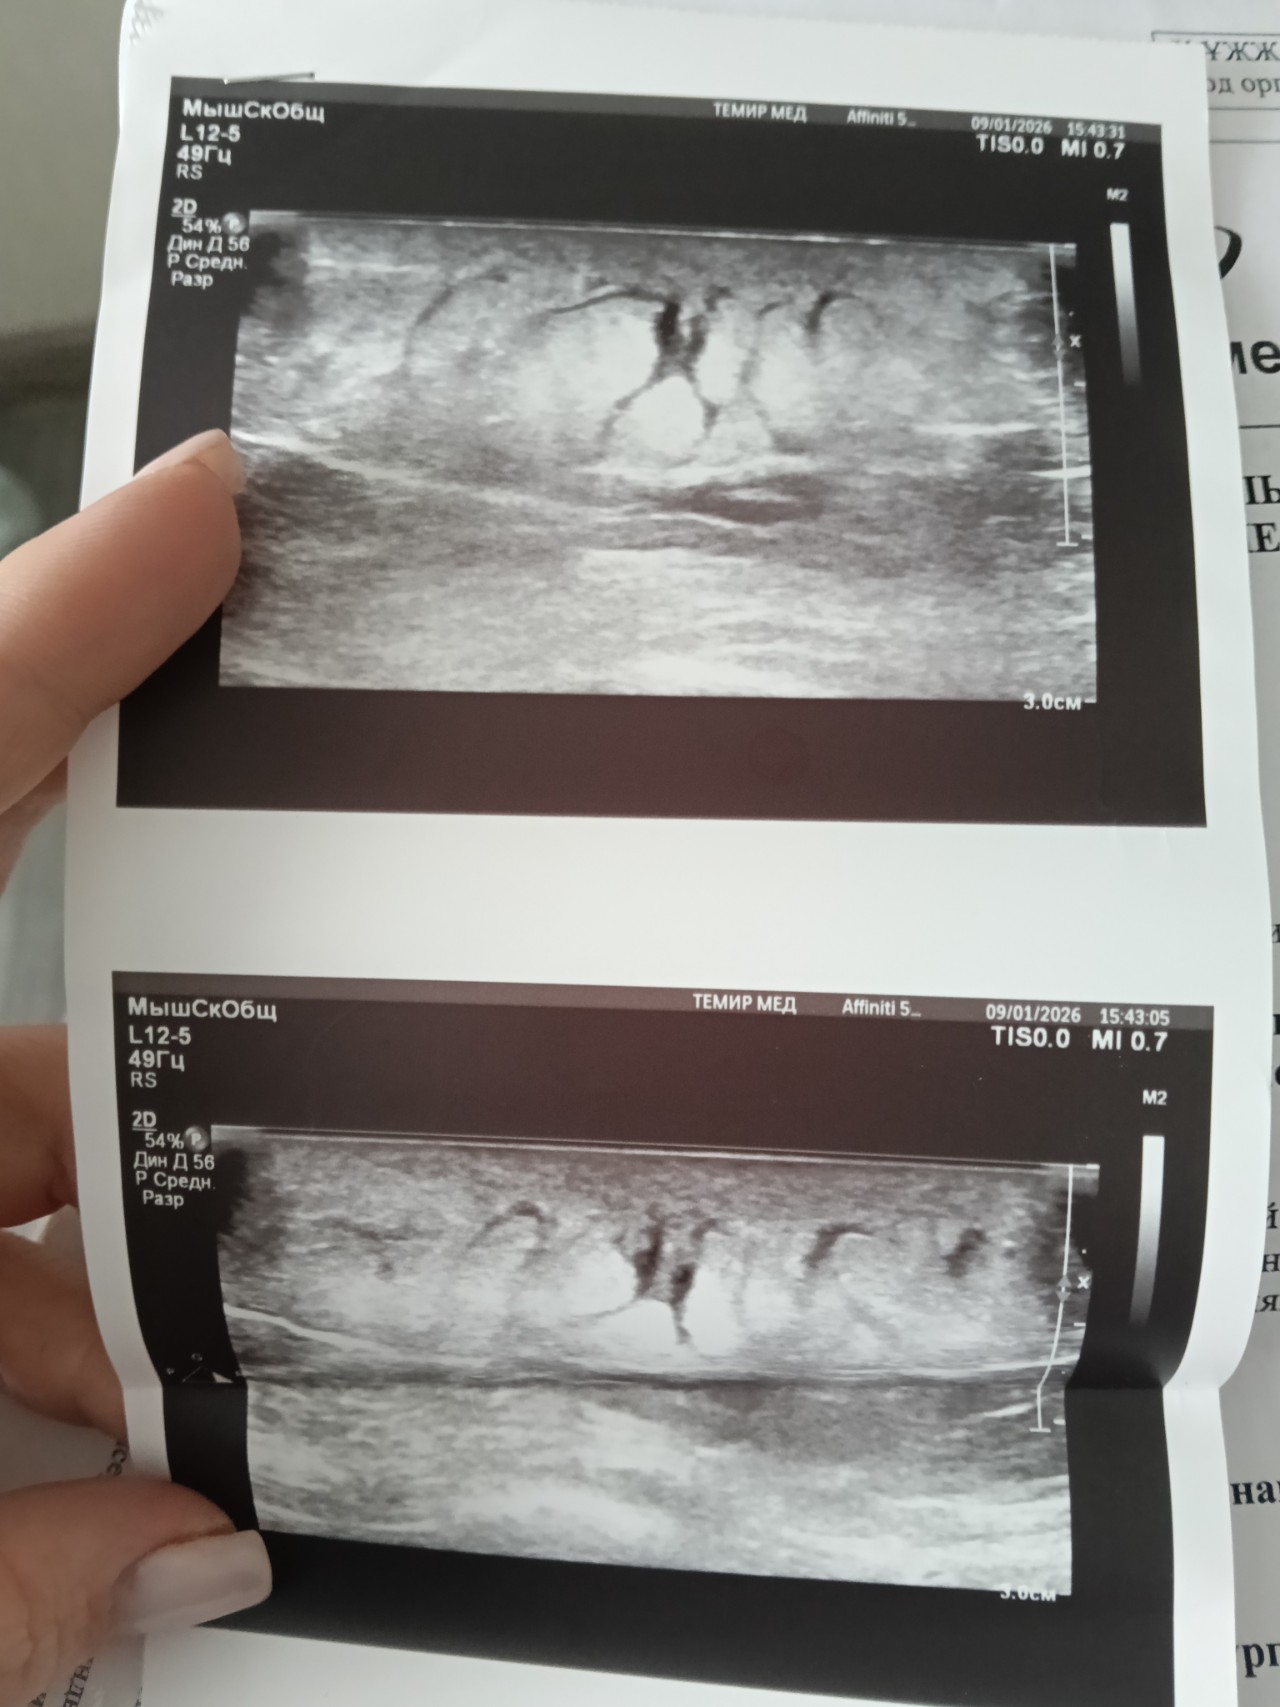

фото УЗИ тоже прикреплю

Здравствуйте, в конце декабря нащупала у себя сбоку справа в районе ребер небольшое уплотнение, которое немного зудилось и шелушилось, благополучно о нём забыла, так как больше никаких симптомов не было, в середине января это уплотнение дало о себе знать, покраснело, увеличилось в размере, начало выступать над кожей, горячее на ощупь, обратилась к хирургу, было назначено курс антибиотиков внутримышечно и мазь Вишневского местно, диагноз поставил Подкожный инфильтрат, сходила на УЗИ мягких тканей сказали что образование внутрикожное и подтвердили диагноз хирурга, после начала лечения образование быстро уменьшилось, и в течении этого месяца вообще исчезло, повторно пошла к хирургу он сказал что это уже Липома, пока наблюдать и если будет расти нужно будет удалить. 25 февраля снова увеличилось образование, те же симптомы. Подскажите пожалуйста правильный ли диагноз поставил хирург? Или нужно ещё дообследовать (пройти МРТ) ? очень переживаю